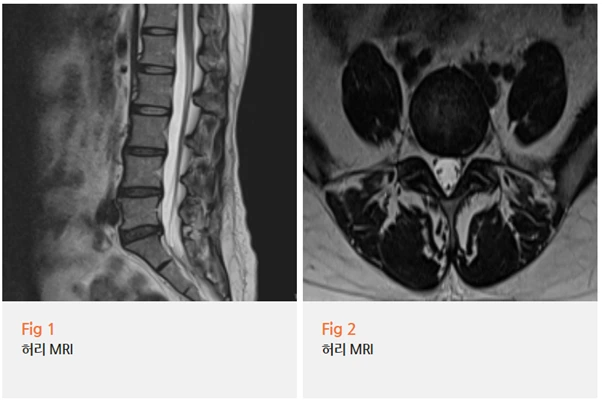

MRI 결과를 보니까 요추 추간판 탈출증, 즉 허리 디스크가 확인됐어요.

그리고 위치를 보니 왼쪽 다리로 가는 신경근을 압박하고 있는 상태였어요.

이게 바로 좌측 종아리 통증의 원인이었던 거예요.

허리 증상은 없었지만, 신경근이 눌리는 위치와 정도에 따라서 이렇게 하지에만 증상이 나타날 수 있어요.

의학적으로는 이를 신경근병증이라고 합니다.